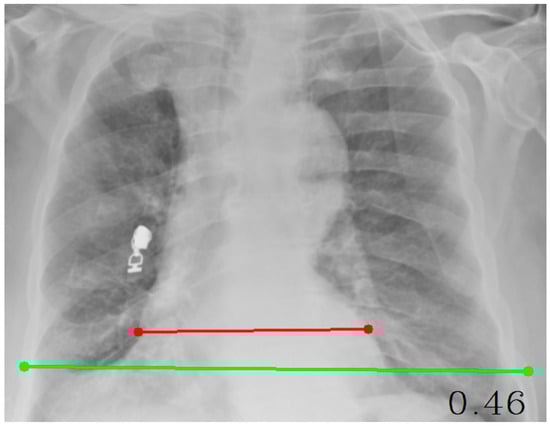

| CTR (Cardiothoracic Ratio) | cv2, numpy, tkinter | Calculates the ratio of cardiac width to thoracic width | Involves point selection and distance measurement |